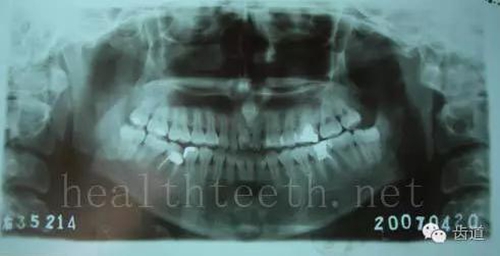

智齒反復(fù)發(fā)炎造成的頰瘺,膿腫切開引流后面部會(huì)留疤

81.jpg